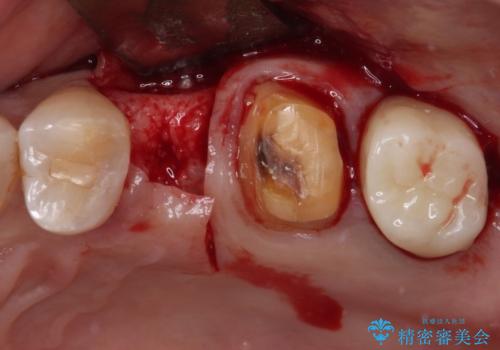

- 治療をおこなって以来、クラウン周りの歯肉から出血が続くとのことで来院された患者様です。

診察を行ったところ、クラウンと歯の境目が不適合で汚れが溜まりやすく、炎症を起こしている状態でした。

治療を終えたばかりですが、出血を改善するためには作り直しが必要と判断し、オールセラミッククラウンにて補綴治療することとしました。